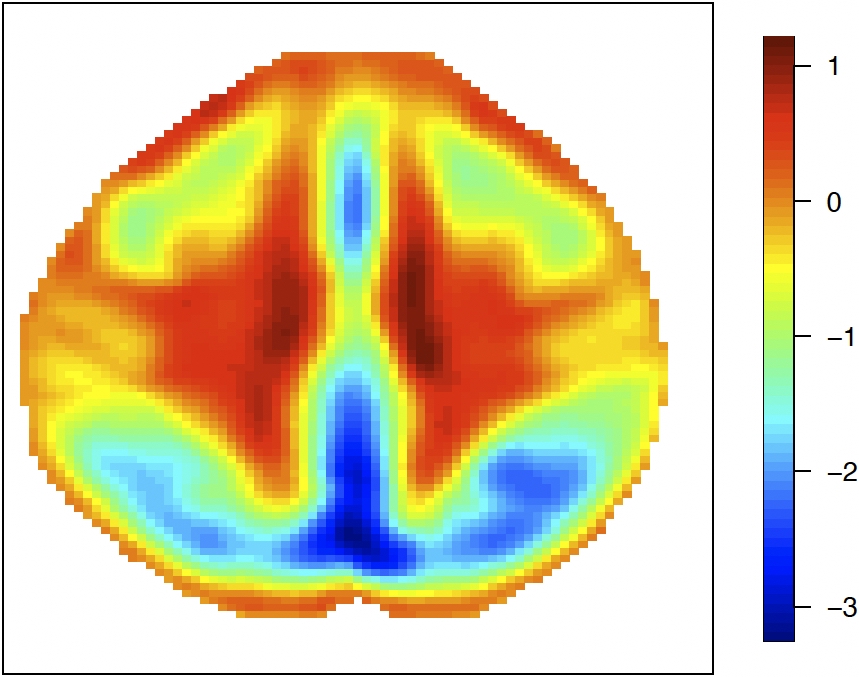

For the Hilbert-valued component, we first consider a 2D imaging setting. To mimic the full complexity of the real data and illustrate the performance of the proposed method in a challenging scenario with complicated patterns, we use the leading empirical basis functions obtained from the real data analysis in Section 6. To be specific, we construct the imaging data as Zi(s1,s2)=j=16λj1/2Uijϕj(s1,s2)Z_{i}(s_{1},s_{2})=\sum_{j=1}^{6}\lambda_{j}^{1/2}U_{ij}\phi_{j}(s_{1},s_{2}) on a 79×9579\times 95 pixel grid, where the eigenvalues (λ1,λ2,λ3,λ4,λ5,λ6)=(3.5,3,2.5,2,1.5,1)(\lambda_{1},\lambda_{2},\lambda_{3},\lambda_{4},\lambda_{5},\lambda_{6})=(3.5,3,2.5,2,1.5,1) and (Ui1,,Ui6)(U_{i1},\ldots,U_{i6})^{\top} follows MVN(06,I6)\text{MVN}(0_{6},I_{6}). The basis functions {ϕj}j=16\{\phi_{j}\}_{j=1}^{6} are the leading six principal component bases that are selected by PVE from the real data analysis; see Section 6.1 for more details. Figure 5.1 (top row) and Figure 6.1 (left three columns) display the plots of these basis functions. We set γ0=1.5ϕ1+ϕ2+2ϕ3+2.5ϕ4+1.5ϕ5+3ϕ6\gamma_{0}=1.5\phi_{1}+\phi_{2}+2\phi_{3}+2.5\phi_{4}+1.5\phi_{5}+3\phi_{6}.

Refer to caption Refer to caption Refer to caption Refer to caption Refer to caption Refer to caption

ϕ1\phi_{1}\penalty 10000\ \penalty 10000\ ϕ2\phi_{2} ϕ3\phi_{3} ϕ4\phi_{4}\penalty 10000\ \penalty 10000\ ϕ5\phi_{5} ϕ6\phi_{6}

ϕ^1\widehat{\phi}_{1}\penalty 10000\ \penalty 10000\ ϕ^2\widehat{\phi}_{2} ϕ^3\widehat{\phi}_{3} ϕ^4\widehat{\phi}_{4}\penalty 10000\ \penalty 10000\ ϕ^5\widehat{\phi}_{5} ϕ^6\widehat{\phi}_{6}

Figure 5.1: Comparison of true basis functions {ϕj}j=16\{\phi_{j}\}_{j=1}^{6} (top) and their estimates {ϕ^j}j=16\{\widehat{\phi}_{j}\}_{j=1}^{6} (bottom) for a randomly selected iteration with n=2000n=2000 in the 2D imaging setting.

The estimates of the basis functions are shown at the bottom of Figure 5.1, which is selected randomly from a single iteration. The figure shows that with n=2000n=2000 observations, the estimated basis functions (bottom row) closely reproduce both the pattern and magnitude of the true functions (top row), providing empirical validation of Theorem 4. In addition, Table 5.1 presents the estimation accuracy of the six eigenvalues (λ1\lambda_{1} through λ6\lambda_{6}) and the estimated number of eigenvalues under the PVE (m^n\widehat{m}_{n}) criterion. We observe that MSEs for all eigenvalues decrease as sample size increases across both correlation scenarios, demonstrating improved estimation precision with larger samples. The results in Table 5.1 further support the conclusions in Theorem 4 and Corollary 3.